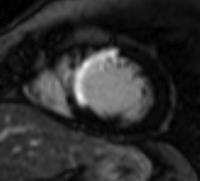

参:19歳の症状のないバスケットプレーヤーで症状がなく、心電図変化を認める症例のMRI画像の変化を示す。Baselineでは14mmの後中核壁の肥厚を認めるのみであったが、三か月後の運動中止では心筋壁の変化は認めなかった。造影MRIを行ったところ遅延造影が軽度肥厚した心筋の局所に認められ、肥大型心筋症と診断された。

参:肥大型心筋症の肥大パターンを見てみると下図のようになる。